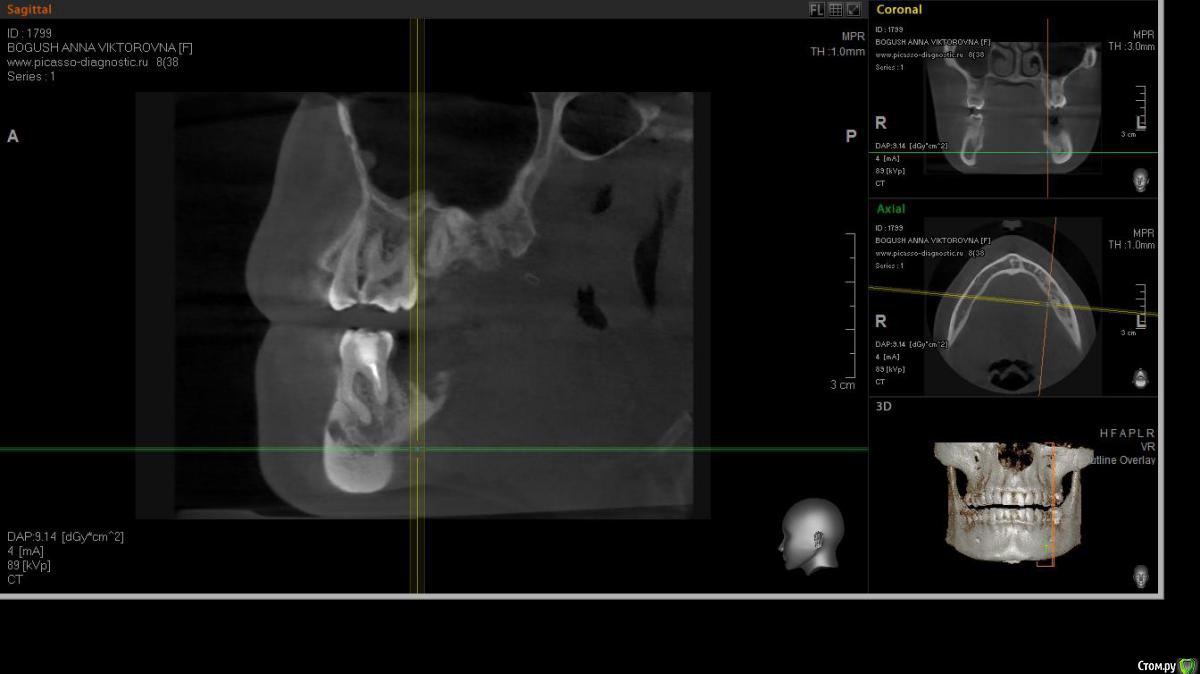

cor Опубликовано 2 апреля, 2016 Поделиться Опубликовано 2 апреля, 2016 Доброго времени суток, коллеги! Каков Ваш прогноз? Удалять пац. совсем не хочет(знакомая). Есть хоть какая то вероятность, что ретрит поможет? <script> </script> Ссылка на комментарий

cor Опубликовано 2 апреля, 2016 Поделиться Опубликовано 2 апреля, 2016 (изменено) гадская вирусятина на компе мешает. Нет конечно желающих. Но если ретрит будет, то делать его буду я. Но слабо верю в положительный исход(( Изменено 2 апреля, 2016 пользователем cor Ссылка на комментарий

St. Опубликовано 3 апреля, 2016 Поделиться Опубликовано 3 апреля, 2016 Доброго времени суток, коллеги! Каков Ваш прогноз? Удалять пац. совсем не хочет(знакомая). Есть хоть какая то вероятность, что ретрит поможет? Вполне есть смысл попробовать. Вероятность есть, только "заживать" будет долго. Ссылка на комментарий

cor Опубликовано 5 апреля, 2016 Поделиться Опубликовано 5 апреля, 2016 Почему?Наверное потому что такие объемные очаги ещё не перилечивал. Но деваться некуда, будем пробовать. Ссылка на комментарий

Л Ю С Я Опубликовано 5 апреля, 2016 Поделиться Опубликовано 5 апреля, 2016 Наверное потому что такие объемные очаги ещё не перилечивал. Но деваться некуда, будем пробовать.Уже не раз писали, что размер не имеет значения)))). Не надо перелечивать очаг. Ваша задача пройти, правильно сформировать, очистить и запаковать каналы, а также правильно восстановить коронковую часть. И будет вам хилинг))) 2 Ссылка на комментарий